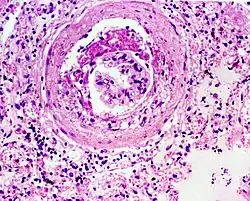

Die Glomerulosklerose (von Glomerulus und altgriechisch σκληρός sklēros „hart“) ist der im Gegensatz zur Glomerulonephritis nicht entzündlich bedingte Teil der Glomerulopathien.[1]

Die Verhärtung entsteht durch Vernarbungen (Sklerose) der Kapillarschlingen der Nierenkörperchen mit Vermehrung und Dickenzunahme des Bindegewebes als Folge aller Erkrankungen mit einem Untergang von Nierengewebe, häufig bei Bluthochdruck und Diabetes mellitus.[2]

Pathologie

Der Pathomechanismus der früher auch als „hypertonische Nephrose des Zuckerkranken“[4] bezeichneten Glomerulosklerose ist komplex:[5]

Vereinfacht führt die Verminderung funktionsfähiger Nephrone zu glomerulärer Hypertrophie und arterieller Hypertonie, und beides führt zur Proliferation von Mesangialzellen. Zusätzliche Faktoren sind Ansammlung von Lipiden mit Makrophagenaktivierung, eine toxisch bedingte Hyperfiltration von Makromolekülen mit Veränderungen der extrazellulären Matrix sowie gefässbedingte Schädigungen des Endothels mit Mikrothromben.